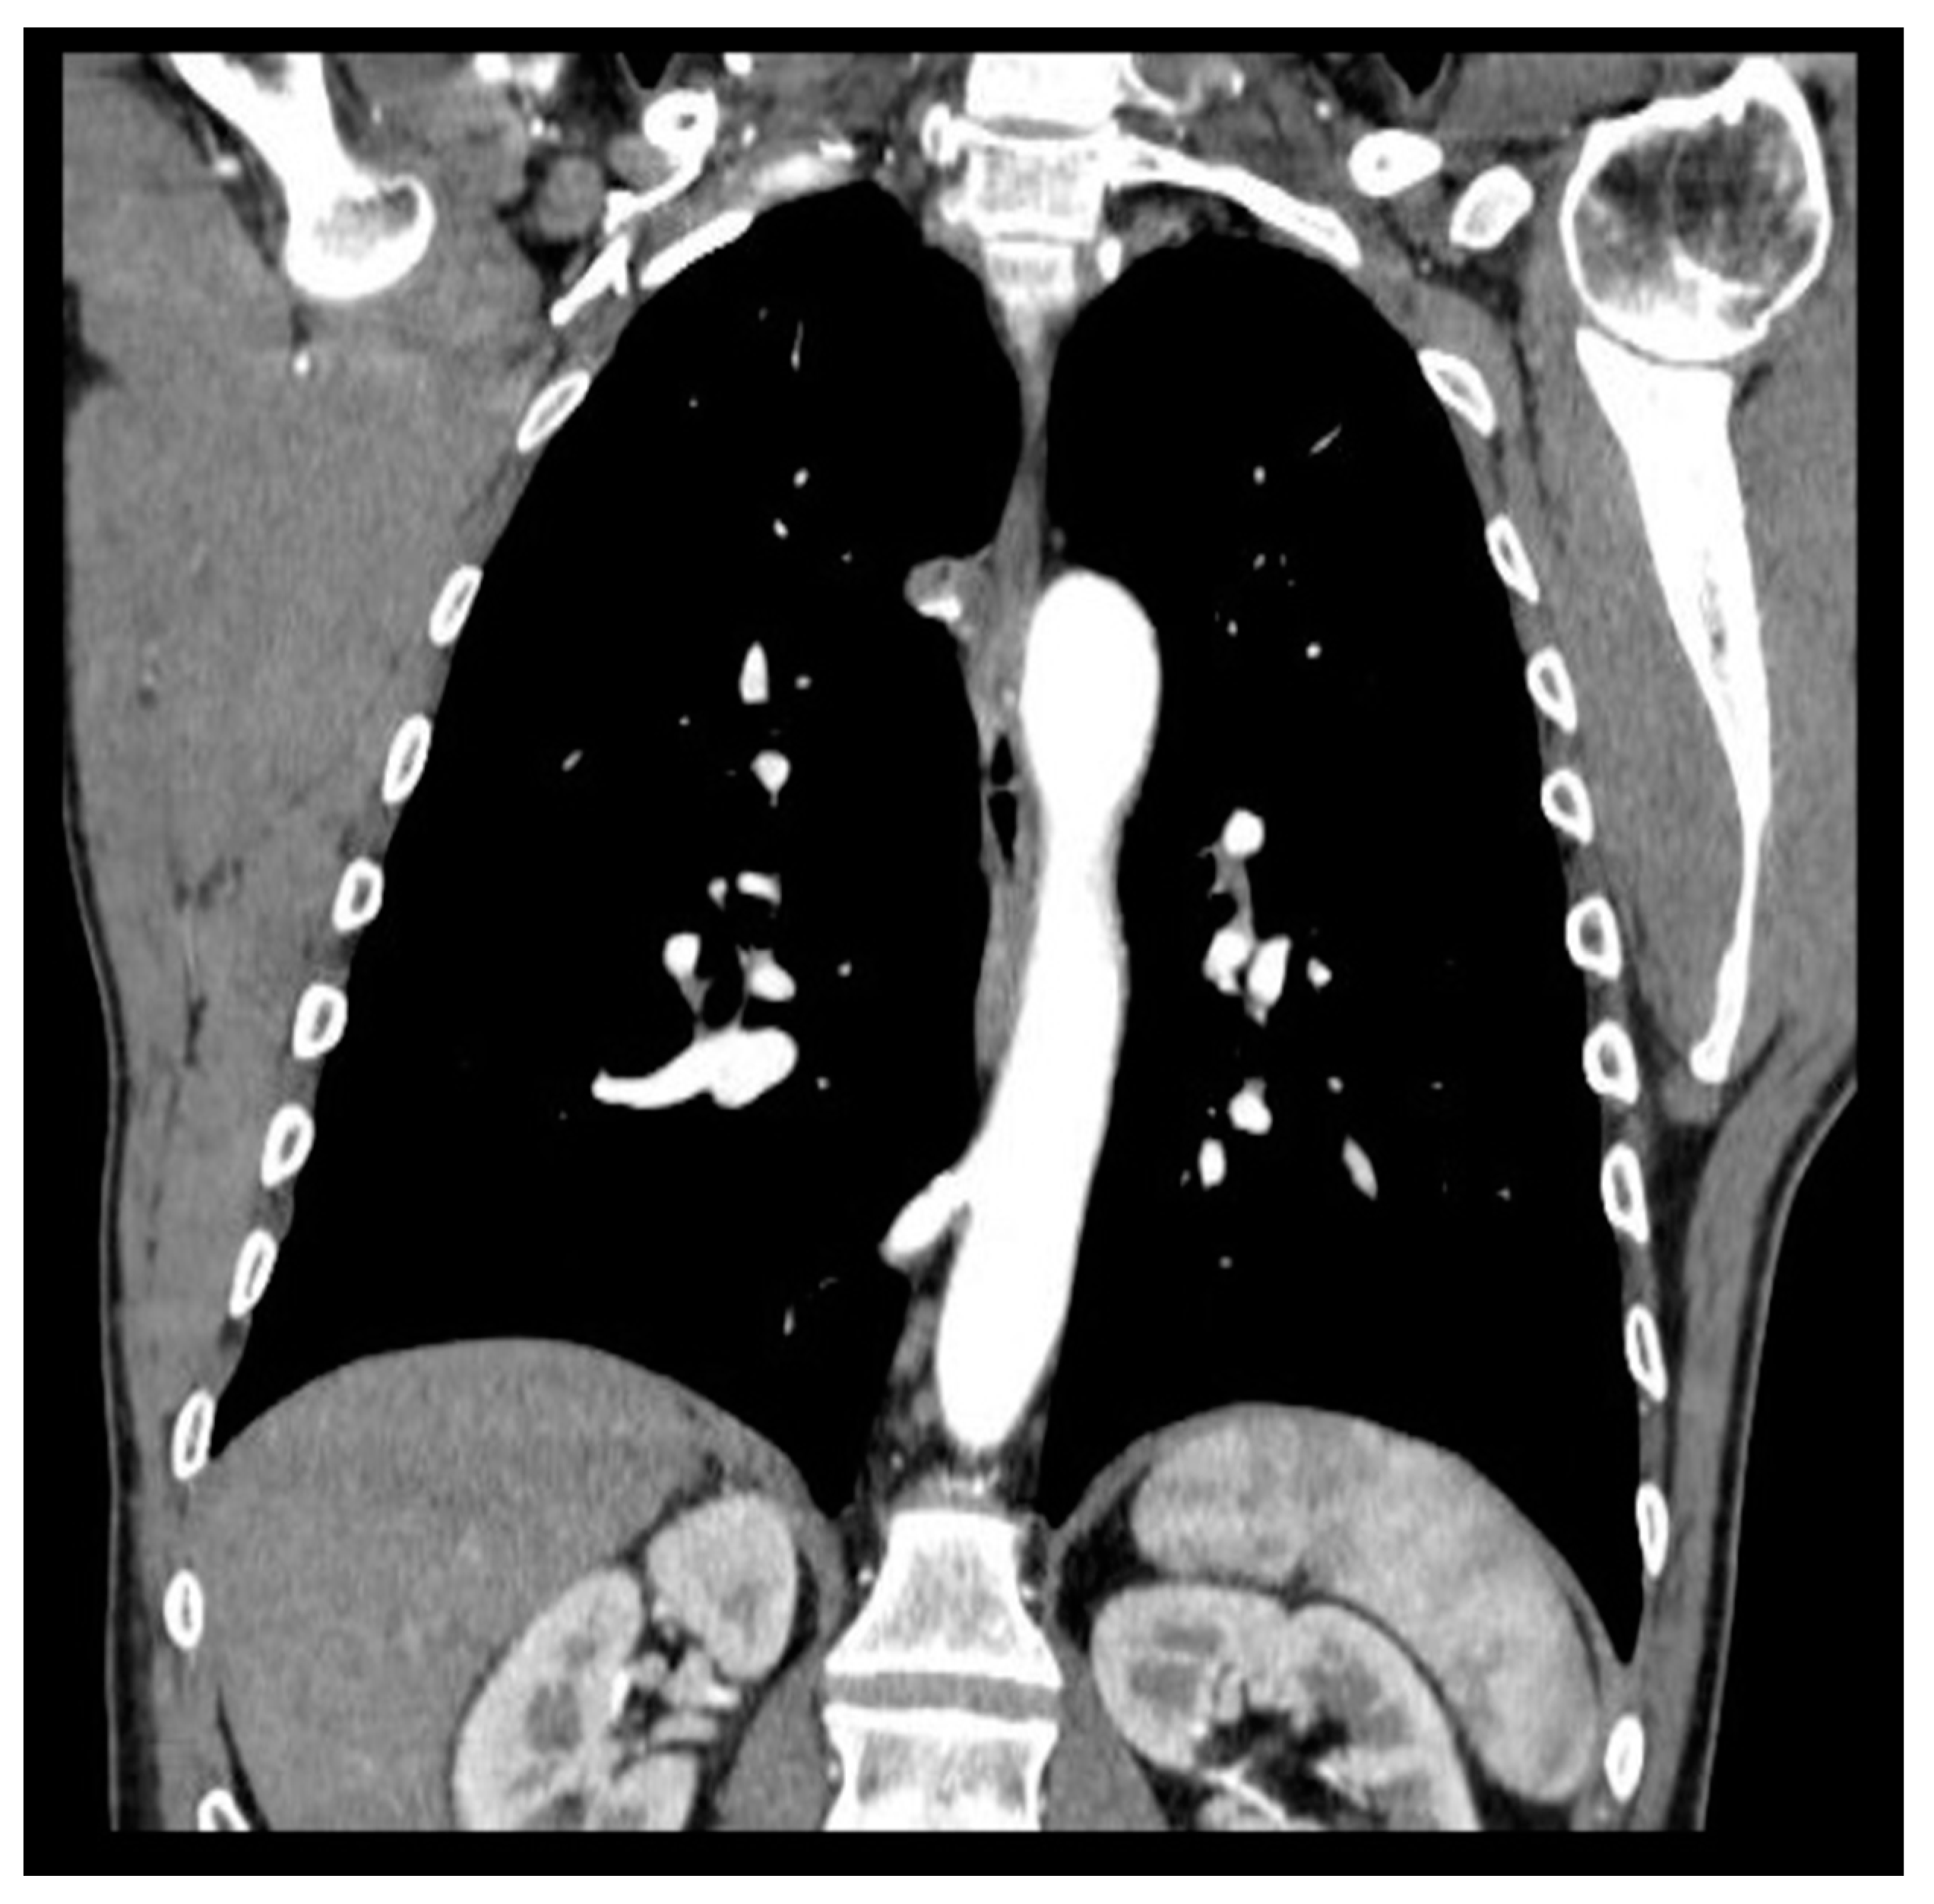

According to literature, patients undergoing parenchyma-saving resection are likely to have early postoperative morbidities such as recurrent pulmonary infection or prolonged air leakage, and in cases of residual lesion, even malignant transformation. [23] The systematic review by Stanton et al. demonstrated a 15% rate of residual disease after segmental resection vs 0% with lobectomy. [16] In our experience a patient treated for CCAM by B9 segmentectomy at the age of 13, developed successive malignant transformation 14 years later (bilaterally metastatic adenocarcinoma) in the residual right lower lobe, primarily identified by respiratory symptoms occurrence (productive coughing) and radiological evidence of lung cancer abscess (Figure 3). In fact, performing subtotal lobectomy or segmentectomy or at worst, an atypical resection, would risk leaving lesions remnants that could later develop in lung cancer.

Figure 3. lung cancer abscess in the residual right lower lobe in a patient treated with pulmonary segmentectomy for CCAM.